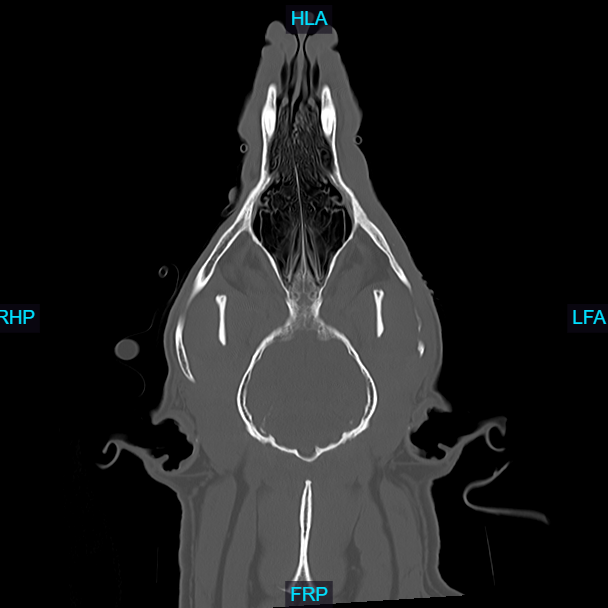

Computed Tomography (CT), also known as a CAT scan, is an advanced imaging technique that combines X-ray technology with computer processing to generate detailed cross-sectional images of an animal's internal structures.

The animal is typically sedated or anesthetized to remain still during the procedure, ensuring high-quality images. Special positioning aids may be used to maintain the correct posture. The animal is placed on a motorized table that moves through a circular opening of the CT scanner. The scanner consists of an X-ray tube that rotates around the animal, emitting X-rays from different angles. Veterinarians and veterinary radiologists analyze the CT images to identify abnormalities such as tumors, fractures, organ diseases, and other conditions. The high-resolution images allow for a detailed examination that is often not possible with traditional X-rays.

- Evaluating complex fractures, joint abnormalities, and spinal disorders.